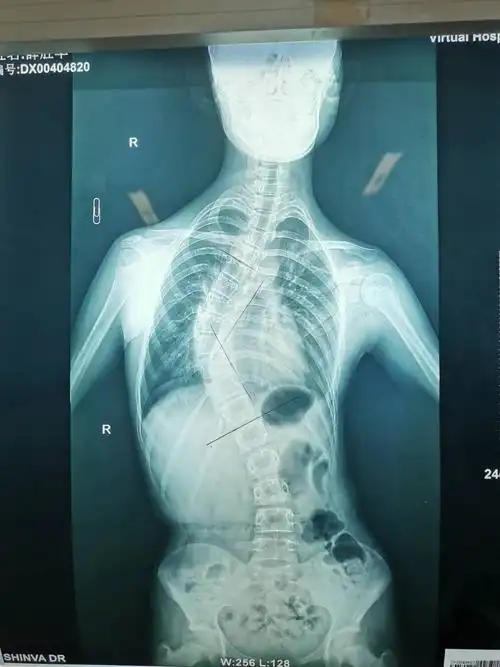

最近完成的一例特发性脊柱侧弯